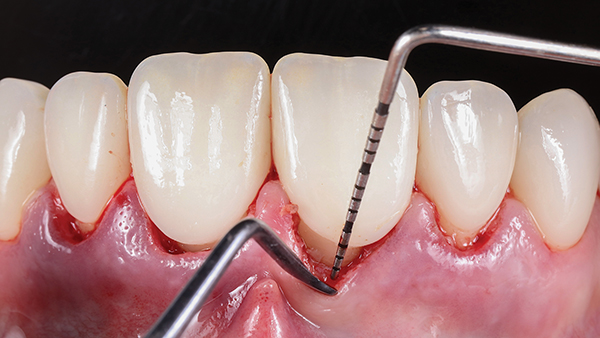

After making "depth cuts" through the mock-up, a gingivectomy was performed on the four maxillary incisors. Fine diamonds, gentle pressure, and copious water irrigation limited trauma to vital teeth during preparation. Smooth preparation surfaces and margins enabled optimal fit of the restorations, which is directly correlated with superior clinical success.14 Similarly, the widespread notion that enamel surfaces prepared with coarse diamonds may improve adhesion has long been defied; smooth enamel preparation surfaces, before phosphoric acid-etching, provide significantly better bond strength.15 Enamel chisels were used to finalize micro-marginal zones, making them sharp and visible for the CAD designer and for optimized marginal fit (Figure 13). Proper soft-tissue retraction is needed for an ideal digital impression with an intraoral scanner to create a high-definition and precision digital model. Provisional restorations were inserted after the preparation.

Fig 13. Enamel chisels were used to finalize micro-marginal zones.

Figure 13